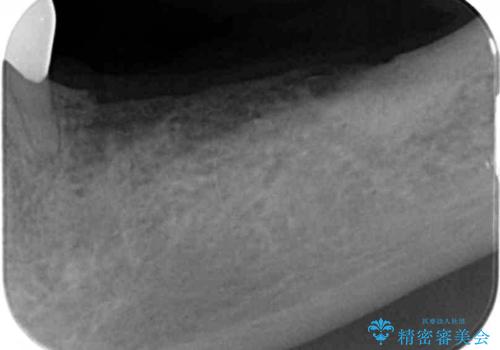

チタンカスタムアバットメントを用いた清掃性の高いインプラント治療

- 喪失した奥歯のインプラント治療を希望され来院されました。

清掃のしやすさと審美性・強度に優れるチタン製カスタムアバットメントとジルコニアクラウンによる補綴治療を計画します。